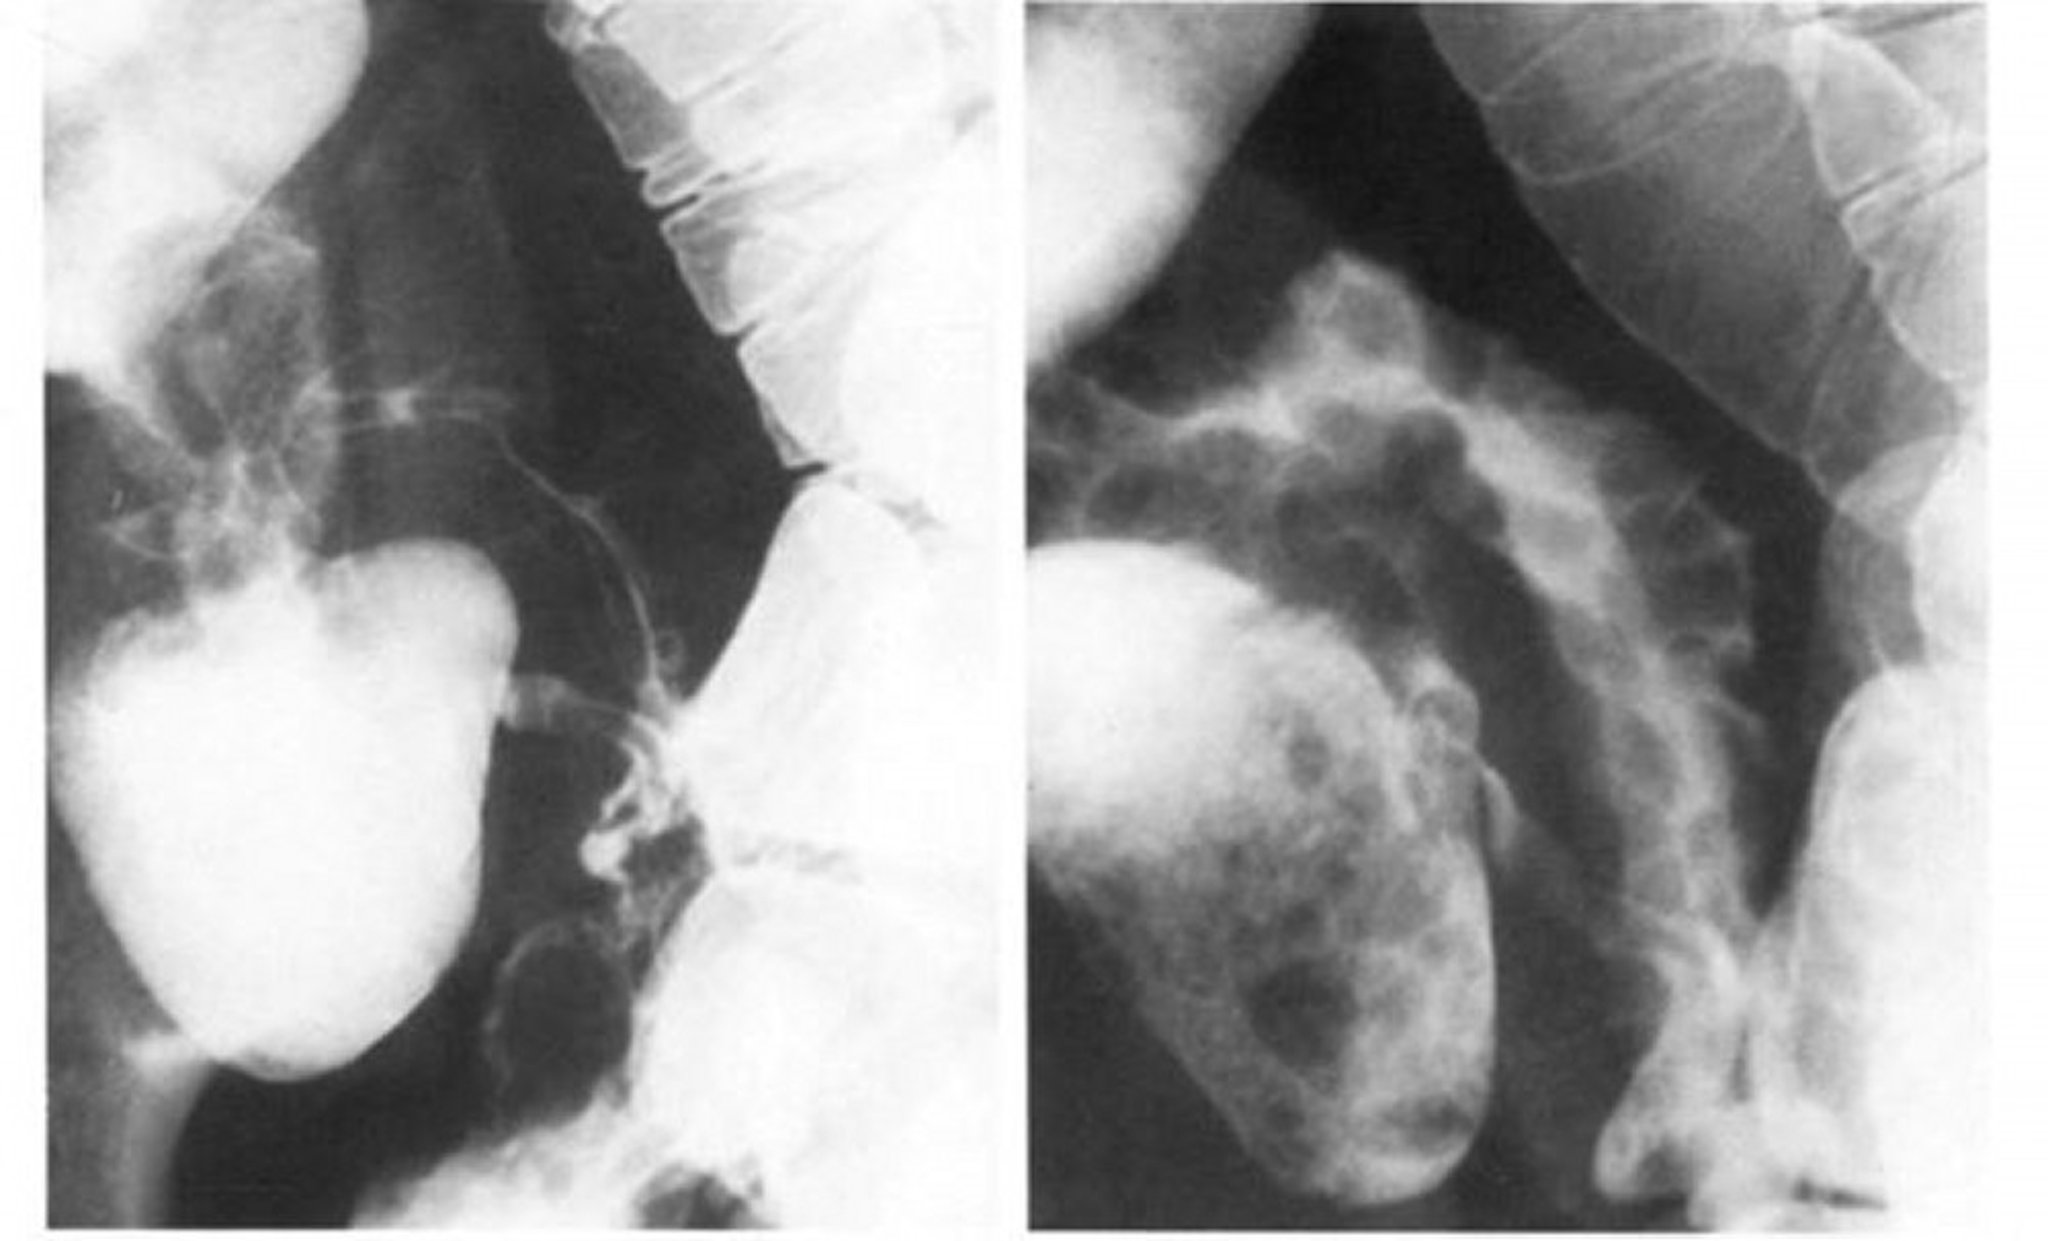

Small-Bowel Follow-Through of Crohn Disease Showing String Sign

The left image shows the spasm obliterates the cobblestone pattern of the terminal ileum, which is best seen in double contrast in the right image.